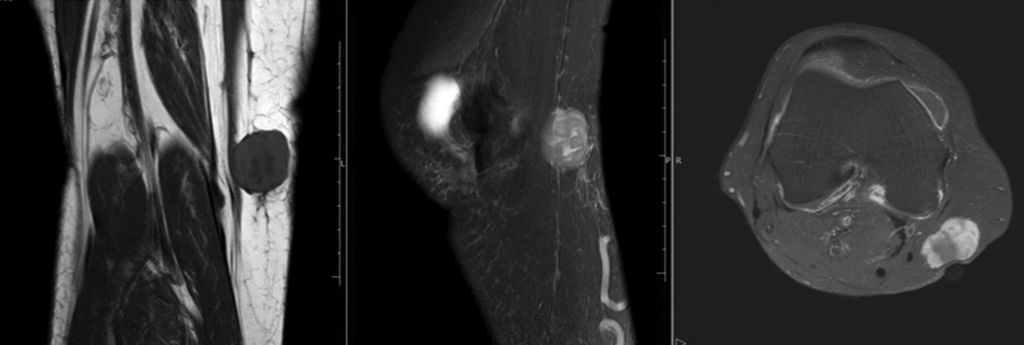

A. Sarcoma de Membros (Partes Moles):

- Imagem: A Ressonância Magnética (RNM) é o padrão-ouro para avaliar compartimentos e planejar a cirurgia. A Tomografia (TC) é usada inicialmente e para estadiamento (tórax).

- Biópsia: SIM! É mandatória antes da cirurgia definitiva para massas suspeitas (>5cm, profundas). O método de escolha é a Core Biopsy (agulha grossa – Trucut), que define o diagnóstico em 97% dos casos. A incisão deve ser longitudinal ao membro, pois o trajeto da biópsia precisará ser removido na cirurgia.